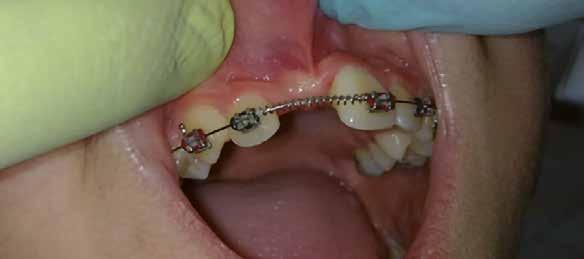

sok korrigálása, valamint az impaktálódott fog előtöréséhez szükséges hely megteremtését követően, egy merev acél ív segítségével stabilizáltuk a fogakat. Ezt követően elvégeztük a jobb felső nagymetszőfog sebészi feltárását. A fog koronáját csupán lágyrész borította, ezért nem volt szükség a csontállomány elvételére. A felszabadítás során egy 975

nm-es hullámhosszon pulzáló üzemmódban alkalmazott lézert használtunk (LaserHF standard, Hager & Werken). A teljesítménye 3 W, az aktív ciklus-idő 50%-os, a vezetőszál átmérője pedig 0,4 mm volt (2. ábra). A lézert 150 másodpercen keresztül alkalmaztuk. A fogat borító lágyrészek eltávolítását követően egy láncos brekettet rögzítettünk a metszőfog bukkális felszínére. A műtétet követően nem tapasztaltunk vérzést, nem alakult ki oedema, valamint a páciens sem számolt be fájdalom vagy bármely egyéb kellemetlenség fennállásáról. A felszabadítást követően a páciens minden hónapban háromszor jelent meg a felszabadított területre ránövő lágyrészek és az íny lézeres eltávolítása céljából. A beavatkozások során ugyanazt a lézer készüléket használtuk, mint amivel a felszabadítást végeztük. Közvetlenül a felszabadítást követően megkezdtük a fog finom extrudálását a láncos breketthez kötött füzérgumi segítségével.

2. ábra: Az impaktált fog lézerrel asszisztált sebészi feltárása. 3. ábra: A kezelés megkezdését követő 15. hónapban megfigyelhető a sikeres felszabadítást, fogmozgatást és pozicionálást követően látható állapot.

6 hónapon keresztül tartott. Ennek megfelelően a fog körül található szövetek a felszabadítás, valamint a havi kontrollok során 975 nm-es (több mint 25 J/cm2 energiasűrűség) és 660 nm-es hullámhosszúságú (12–18 J/cm2 energiasűrűség) lézersugarakkal is megvilágításra kerültek. Az impaktálódott fogat megközelítőleg 7 hónap alatt tudtuk megfelelő pozícióba mozgatni (3. ábra). Az orthodoncia kezelés aktív szakasza 18 hónapon keresztül tartott. A fogívek végső nivellálását és a fogak végleges pozícióba rendezését 0.018 × 0.025-ös acélívekkel végeztük.